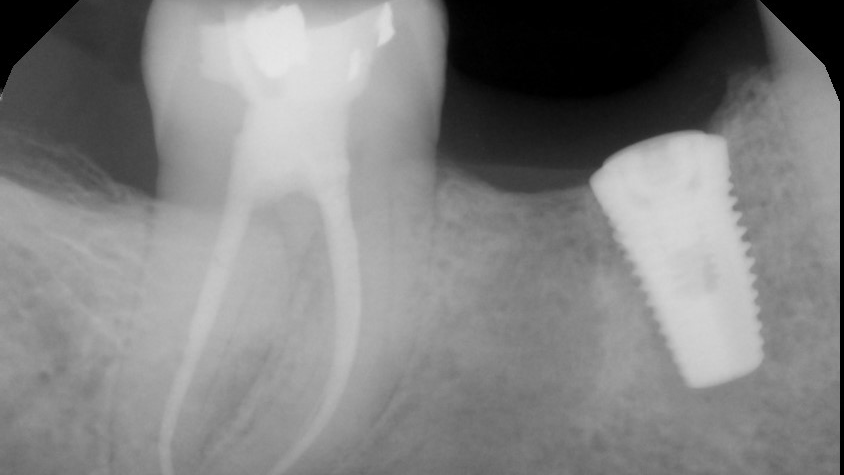

x-ray of a dental implant

This article reviews the top five drug classes beyond bisphosphonates that have demonstrated a clinically significant association with MRONJ, summarizing mechanisms, pharmacologic...

Dec. 2, 2025